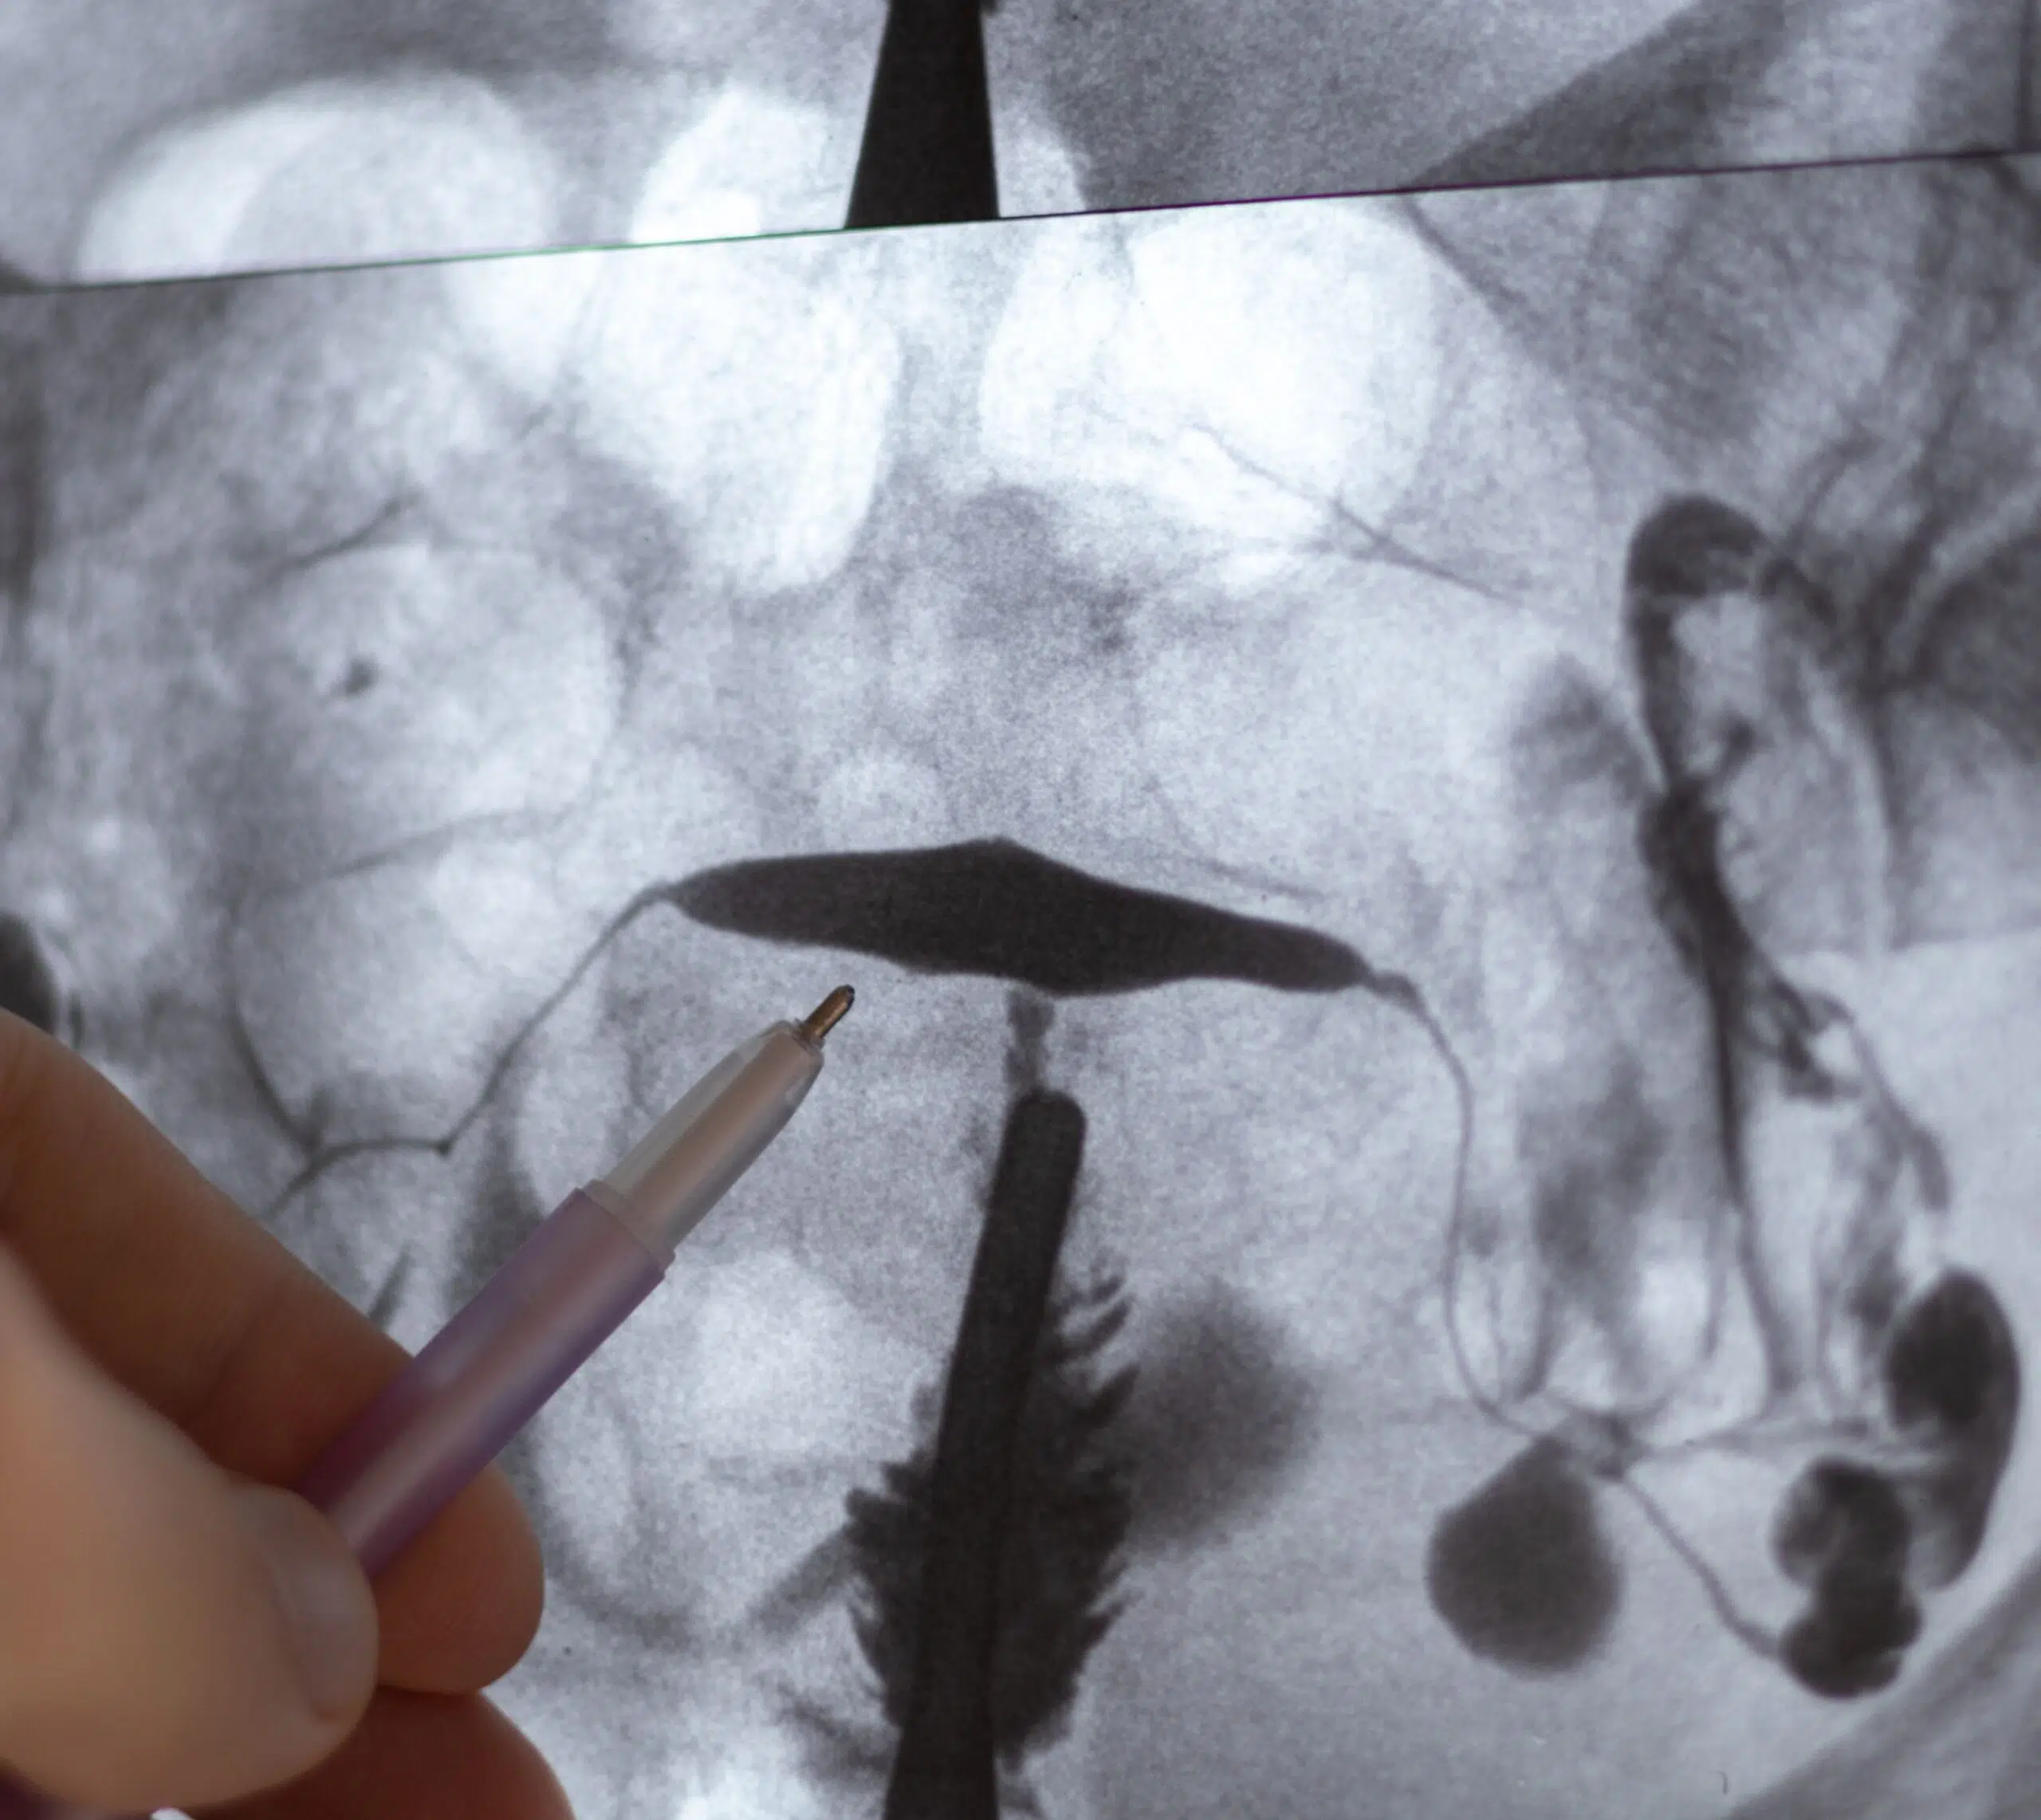

Radiographie pelvienne avec un stylo pointant vers la radiographie - hysterosalpingographie| Imagerie Cardinet | Région Parisienne

L’hystérosalpingographie (HSG) est une technique d’imagerie médicale principalement utilisée pour évaluer la perméabilité des trompes de Fallope et la morphologie de l’utérus.

• Produit de contraste : Un produit de contraste iodé est injecté dans la cavité utérine via le col de l’utérus. Ce produit remplit l’utérus et les trompes de Fallope, permettant de visualiser leur structure et leur perméabilité sur les images radiographiques.

• Sous contrôle radiographique, des images en temps réel sont prises pour suivre la progression du produit de contraste à travers l’utérus et les trompes de Fallope.